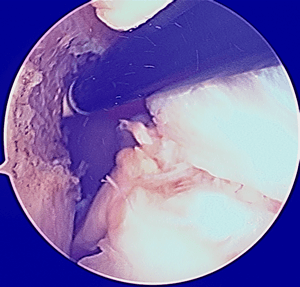

Le fil bleu apparait dans l'articulation, sortant du tunnel fémoral.

La pince passée dans le tunnel tibial, attrape le fil bleu.

Cette photo montre le fil bleu passant du fémur au tibia : il montre le futur positionnement de la greffe du ligament.

Les flèches montre l'orifice des tunnels.